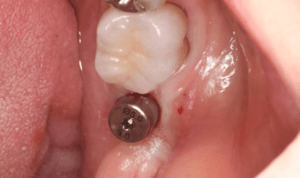

症例写真-1

- Befor

- After

症例写真-2

- 途中経過

| 年齢 | 50代・男性 |

| 主訴 | 右下歯が疼く |

| 治療内容 | ・右下6番インプラント ※1:FGG(遊離歯肉移植術)とは、足りない歯ぐきを上顎から上皮を切り取り移植する外科手術 |

| 治療費 | 合計:902,000円(税込) ■内訳 |

| 治療期間 | 9ヵ月 |

| 治療方針 | 右下の当該歯は歯根破折により保存不可能と診断しました。歯周疾患も伴っていたため抜歯後に骨吸収※1が大きく起こることが予測できました。チタンメッシュ併用骨再生誘導法(GBR※2)を選択しインプラント埋入と同時に行い自然な歯槽骨のラインを再現しました。またGBRを行う際にインプラント辺縁の付着歯肉の減少が起こる為、遊離歯肉移植術(FGG※3)を行い清掃性を考慮した形態に仕上げました。 ■治療方針の解説 治療した右下の歯をレントゲンで撮影したところ根本の部分に黒く写る箇所があり「根尖性慢性周囲炎※1」と診断。また歯周病も進行していました。 ※1 骨吸収・・・歯槽骨という歯を支える骨がなくなっていくこと |

| 担当者所見 | 主訴の右下だけでなく歯茎の腫れ、発赤があり不良補綴や不良充填など他にも治療箇所が多数ありました。プラークコントロールが不良であった為まずはブラッシング指導を行いセルフケアの重要性を理解していただくところからスタートしました。 右下6番の歯はインプラント治療を行なった結果審美的にも機能的にも患者様の満足を得ることができました。骨造成と歯肉移植も行なった為インプラントを支える十分な歯周組織の獲得ができたと思っております。 |